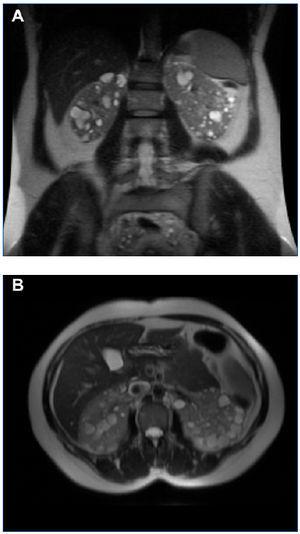

Figura 4. RM del caso 2 en la que se observan riñones aumentados de tamaño, con múltiples quistes grandes, con varios de ellos con signos de hemorragia intraquística (VRT = 1.322 ml). A) Corte coronal. B) Corte axial.